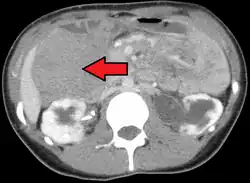

Desmoid tumor as seen on CT scan

Desmoid tumors can occur almost anywhere in the body.[19] They are classified as extra-abdominal, abdominal wall, or intra-abdominal; the last is more common in patients with FAP.[26] Most cases occur in the mesentery, abdominal wall, and extremities.[27] One study has shown extra-abdominal tumors making up 43% of cases, abdominal tumors 49%, and mesenteric 8%, though statistics vary.[16] Pregnancy-related tumors typically arise in the abdominal wall.[28] Tumors located intra-abdominally or in the head and neck have the highest risk of mortality due to the proximity to vital structures.[20]

One analysis has shown a median tumor size of 7.5 cm (3.0 in).[19] Though metastasis cannot occur, the tumors may in some cases be multifocal, with several located in the same body part.[29]

MRI or CT imaging scans are commonly used for monitoring.[47][1]